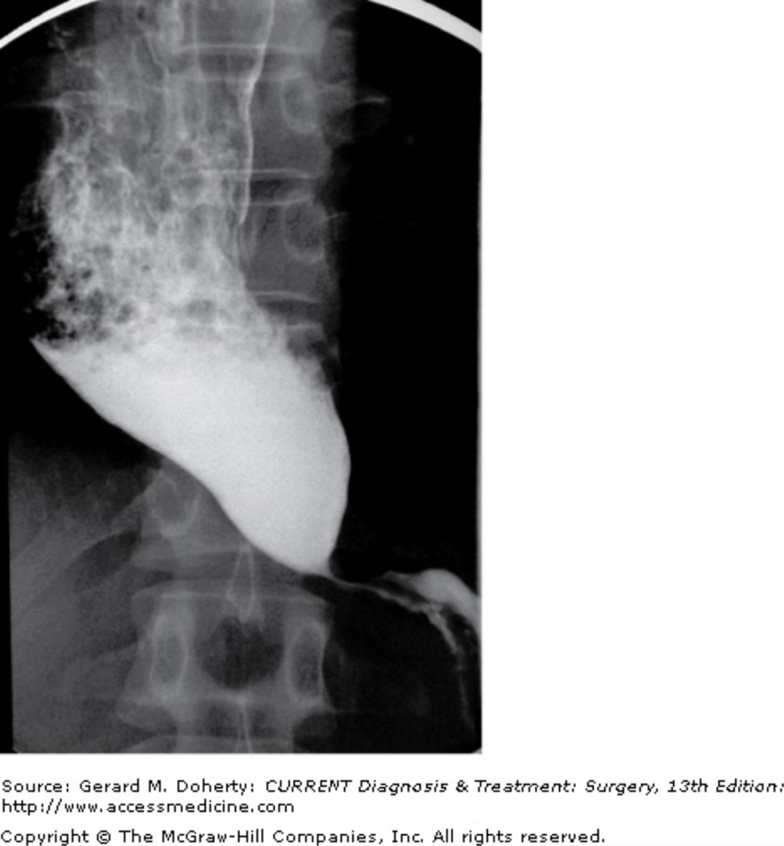

What do you see on this image?

Bird beak sign for achlasia

Scc and adenocarcinoma

Failure of LES to relax due to loss of myenteric (Auerbach) plexus due to loss of postganglionic inhibitory neurons (which contain NO and VIP).

Manometry findings include uncoordinated

or absent peristalsis with high LES resting pressureprogressive dysphagia to solids and liquids (vs obstruction—solids only)